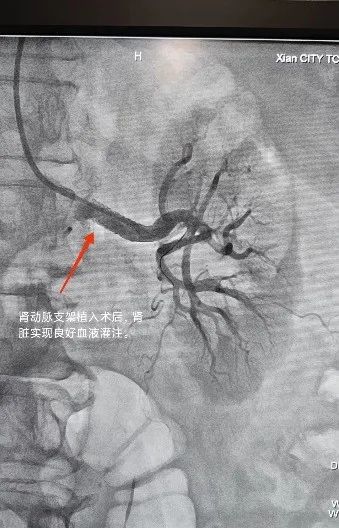

第一例患者既往高血压病史 20 余年,初期使用中效降压药即可控制,近年硝苯地平控释片 30 mg 每天两次、厄贝沙坦 150 mg 每天两次,血压仍然在 160/100 mmHg 左右。排查继发性因素时彩超发现患者左肾动脉重度狭窄及肾脏轻度萎缩,进一步肾动脉造影后明确左肾动脉开口及近段狭窄约 85%。经介入治疗后,肾动脉狭窄解除,血流恢复。

术后患者降压药减半血压即可控制较平稳,随着良好的血液灌注待患侧肾脏功能逐渐恢复,以期降压药进一步减量。